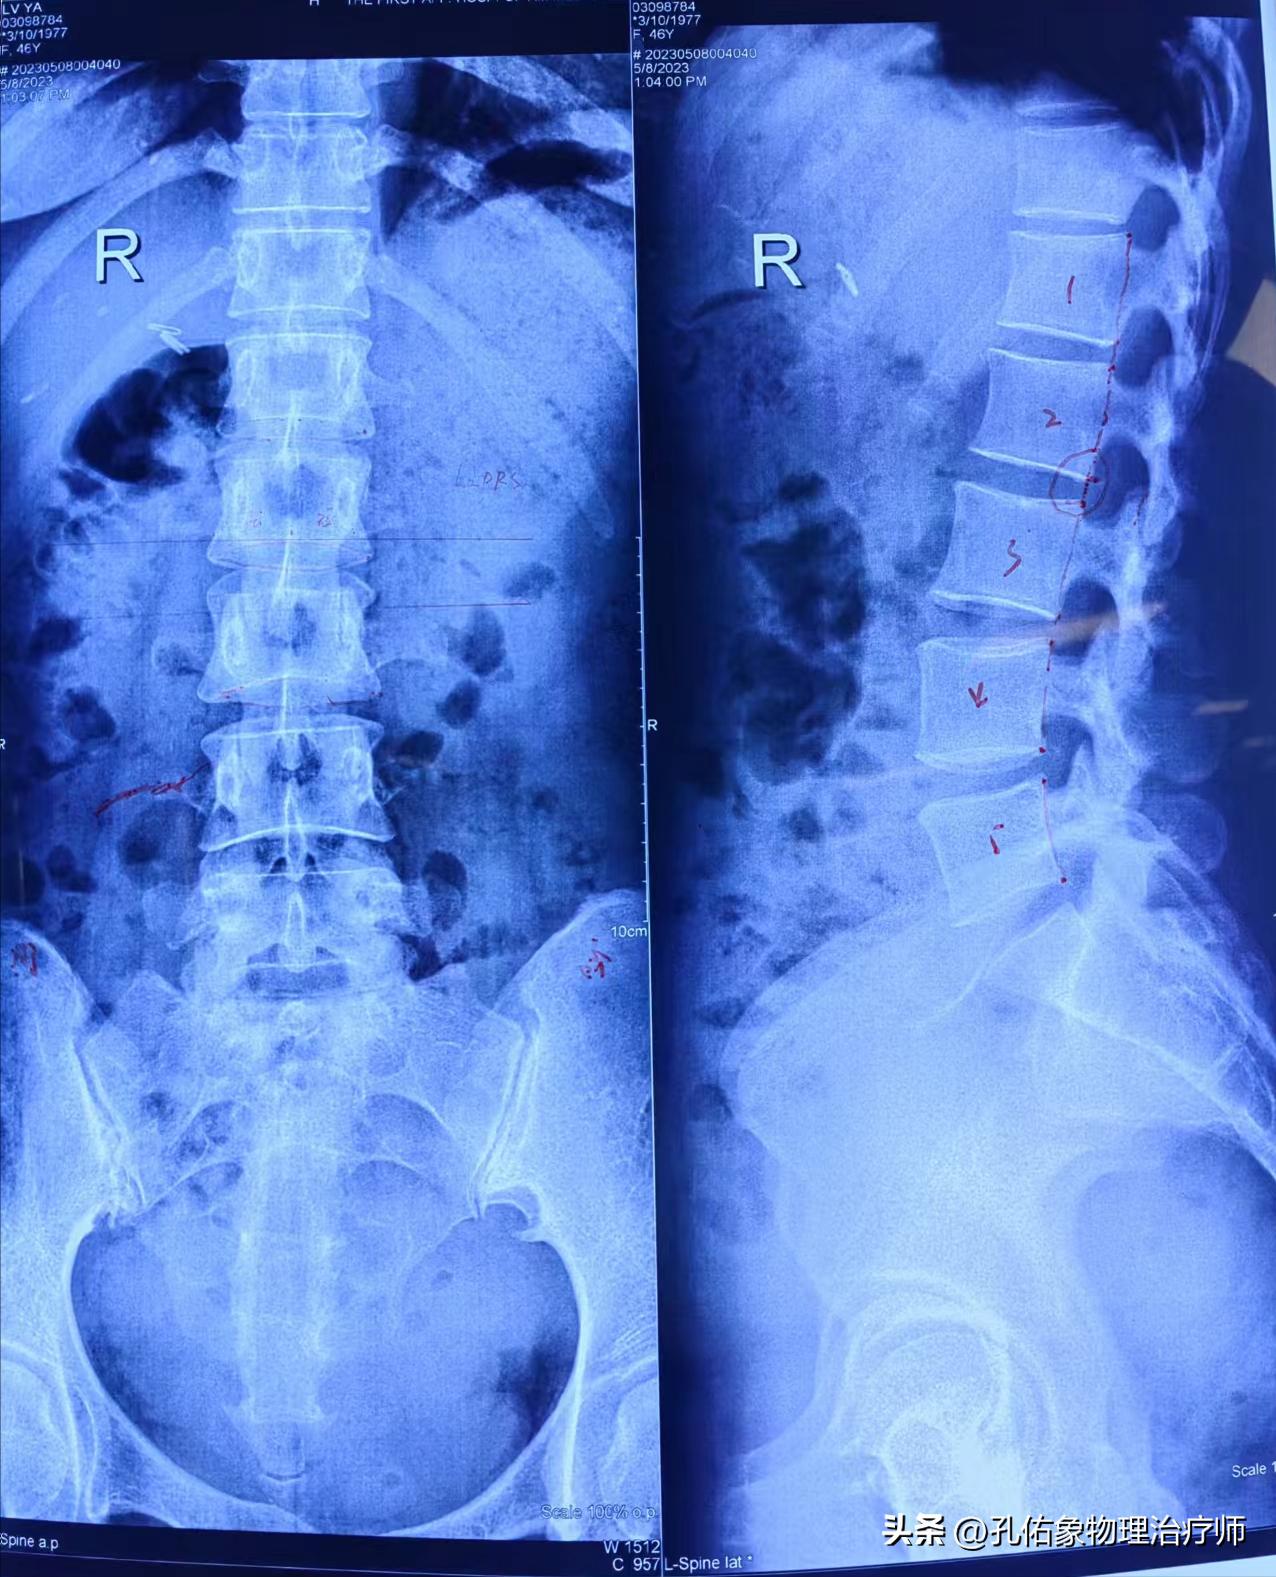

让其拍摄的腰部X片,如下图所示的样子:

阅片得知:双侧骶髂关节钙化,左右两侧骨盆不对称、不等高,脊柱向左侧侧弯,腰2椎体相对腰3椎体后移伴旋转。